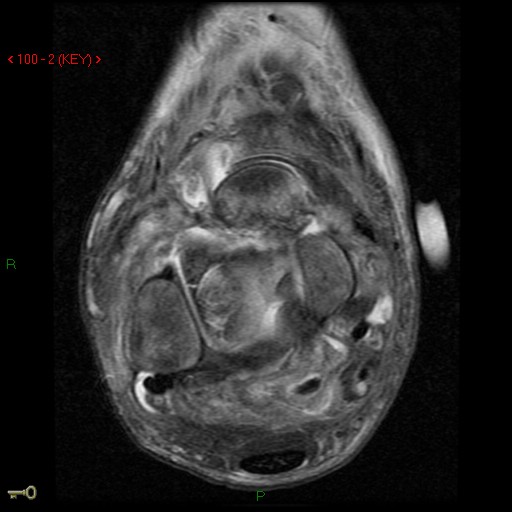

Figure 2 for case AVN talus

Figure 2

Discussion

Likely charcot variant & AVN with talar neck fracture.

AVN talus